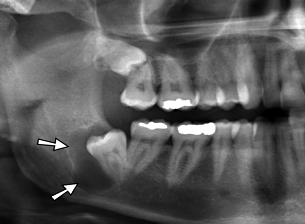

Na imagem abaixo vemos sisos inclusos na arcada superior e inferior, sendo que

o inferior está associado a uma formação cística. Ambos demandam extração: